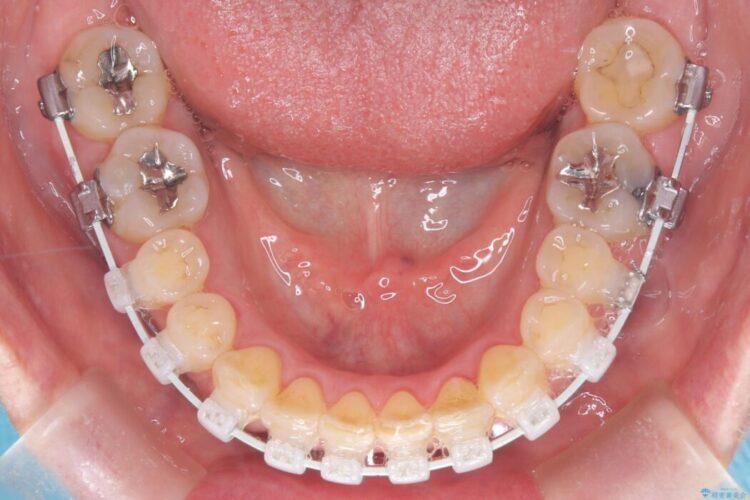

- 矯正装置:審美装置

今回の矯正治療では、歯の色に近い目立たない審美ブラケットとワイヤーを使用しました。

ワイヤー矯正ならではの確実な歯のコントロールにより、当初の計画通り約1年という短い期間で、前歯のガタつきが解消。見た目が美しく整っただけでなく、清掃しやすい機能的な歯並びを獲得していただけました。